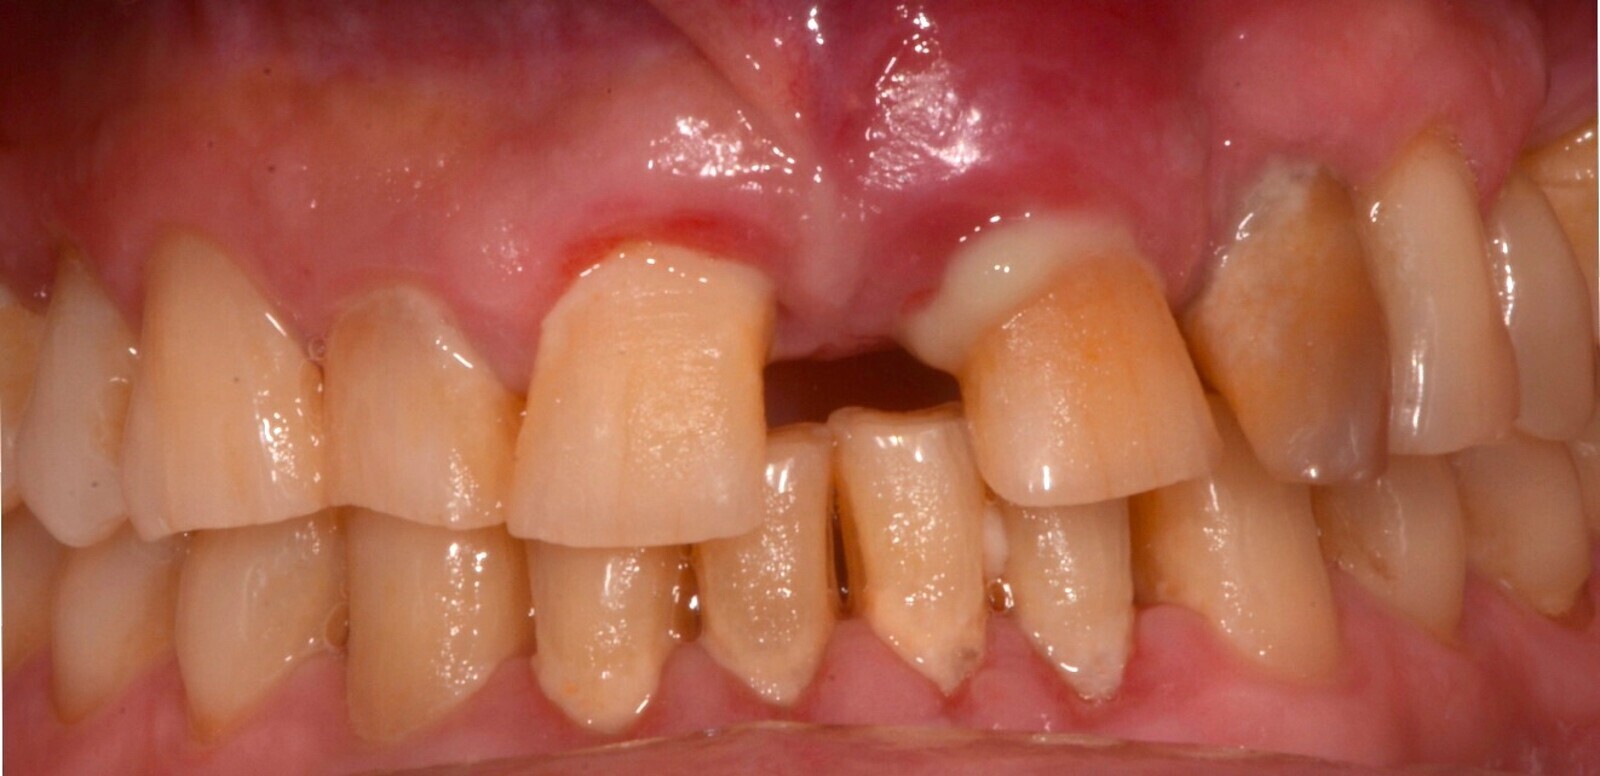

Imagen 1. Situación clínica previa al tratamiento.

Caso donde se observa el volumen, la regeneración y mantenimiento de las tablas vestibulares sin reabsorción ósea, resultando un tratamiento biológico.

En las imágenes se observa el volumen, la regeneración y mantenimiento de las tablas vestibulares de todas las piezas intervenidas, responsables del aspecto de la guirnalda gingival. Sin reabsorción ósea, resultando un tratamiento biológico. “En todo el tratamiento no existe ninguna maniobra clínica, ni del sistema que genere una reacción de defensa que se manifieste como reabsorción, consiguiendo así una integración implanto quirúrgico protético ideal.